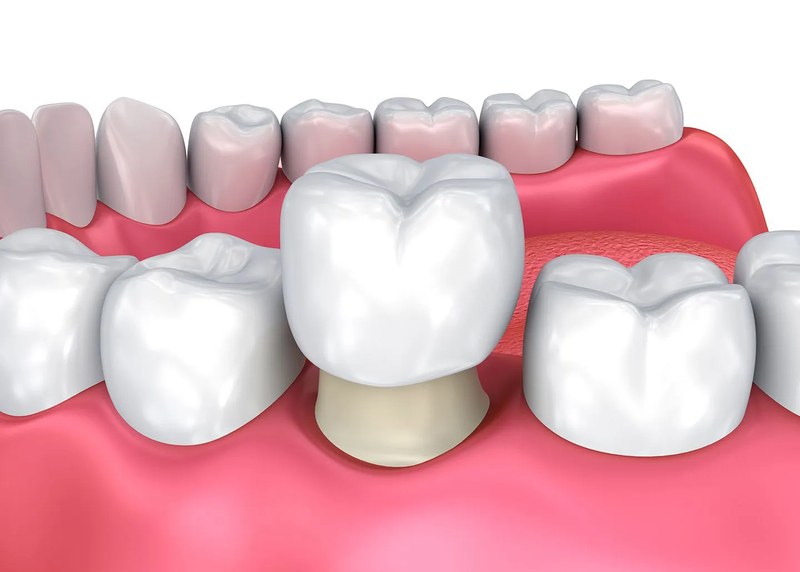

Để kéo dài tuổi thọ của răng sau khi lấy tuỷ, việc bọc răng sứ là một phương pháp được áp dụng. Phương pháp này giúp bảo vệ răng khỏi các tác động từ bên ngoài, đồng thời đảm bảo tính thẩm mỹ và khả năng ăn nhai tốt.